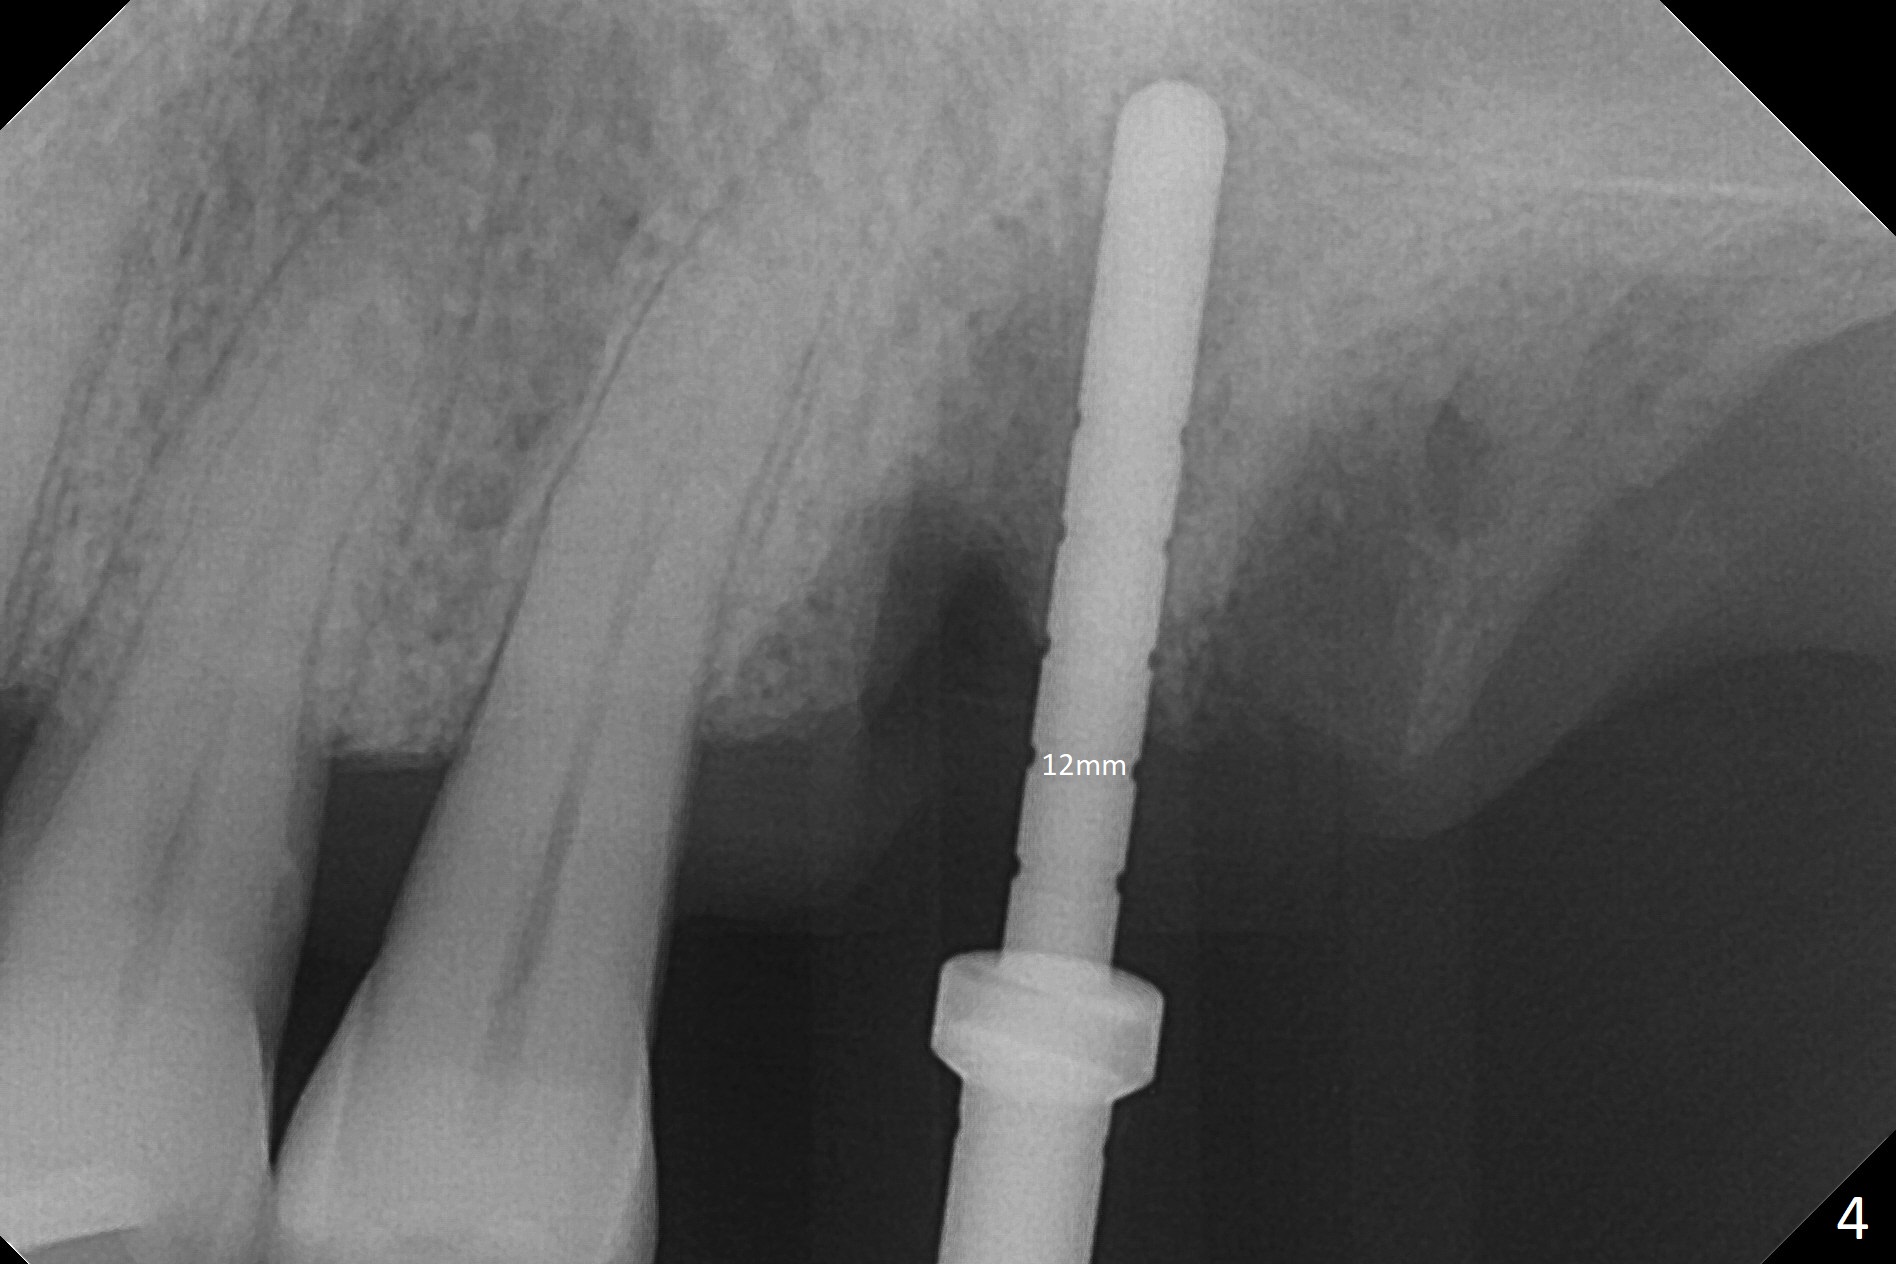

Buccal gingival recession at #14 (Fig.1) is less severe than the palatal one (Fig.2). Without raising the buccal gingiva (Fig.3 B), osteotomy in the septum is established apparently in the middle socket (Fig.3 *, 4). As the osteotomy increases with 3.8 mm drill, the palatal wall of the osteotomy starts to be perforating. When a 4.5x11.5 mm implant is placed, palatal threads are exposed, to which autogenous bone and Vera Graft are placed (Fig.5 *). After placement of a 5.5x5(3) mm abutment, an immediate provisional (Fig.6 P) is fabricated to cover the sockets. If the septal dimension were studied carefully by raising the buccal gingiva slightly, the osteotomy could be initially more buccal so that the palatal thread exposure could be less. When the provisional is removed 1.5 months postop, the implant is exposed palatally. The margin of the provisional is modified so that the implant can be cleaned by the patient using Water Pik. In fact, the healthy gingiva seems to be attached to the implant threads 2 weeks later (Fig.7). The distal implant threads remains exposed 6 months postop; it appears that the distal socket wall has resorbed (Fig.8). The sockets heal 1 year 7 months post cementation (Fig.9).